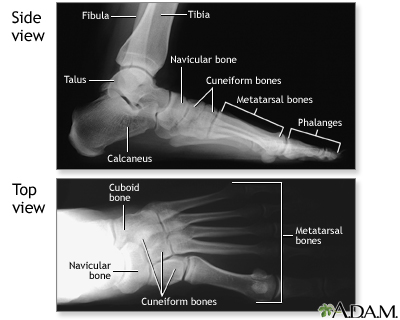

Pain or discomfort can be felt anywhere in the foot. You may have pain in the heel, toes, arch, instep, or the bottom of the foot (sole).

X-rays or MRI may be done to help your provider diagnose the cause of your foot pain.